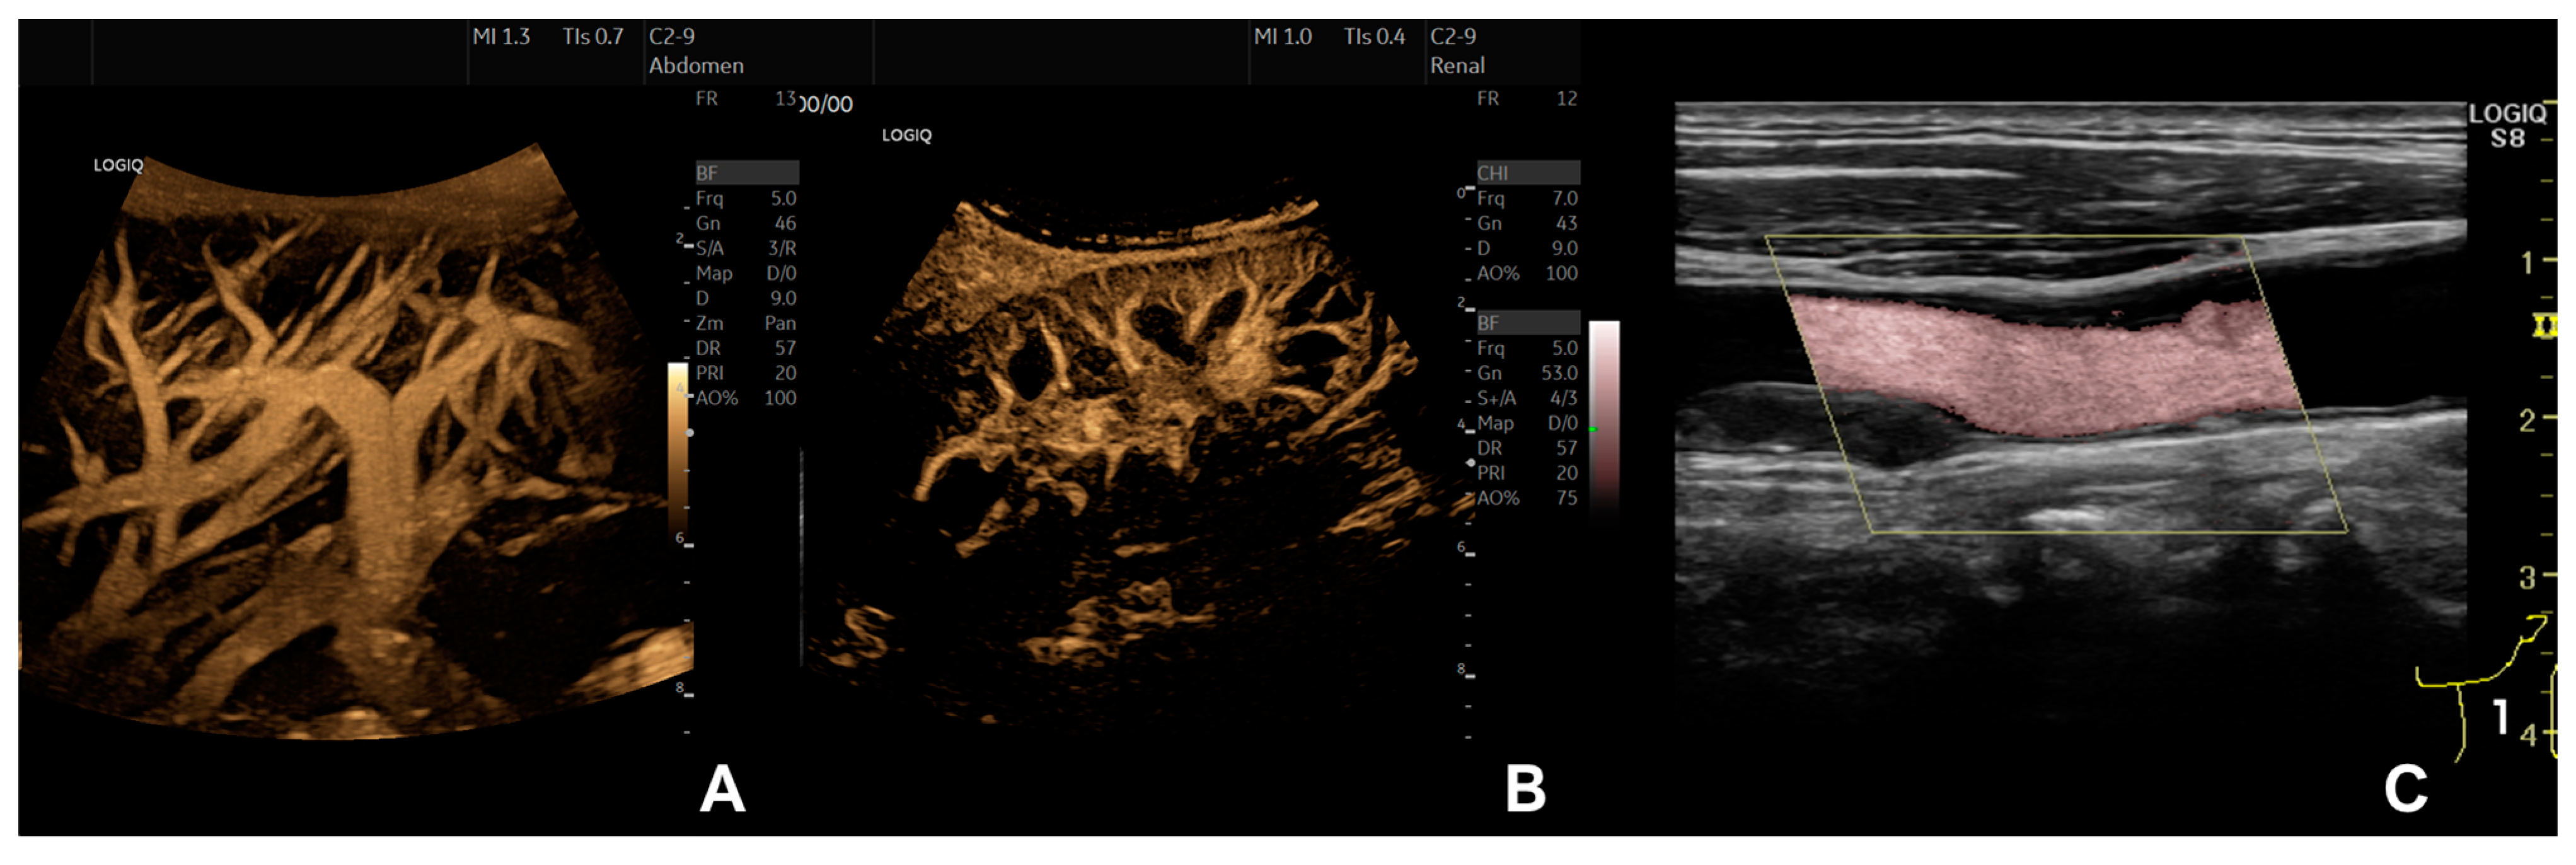

- Jung, E.M.; Kubale, R.; Jungius, K.-P.; Jung, W.; Lenhart, M.; Clevert, D.A. Vascularization of liver tumors—Preliminary results with Coded Harmonic Angio (CHA), phase inversion imaging, 3D power Doppler and contrast medium-enhanced B-flow with second generation contrast agent (Optison). Clin. Hemorheol. Microcirc. 2006, 34, 483–497. [Google Scholar]

- Tola, M.; Yurdakul, M.; Ozbulbul, N.I. B-flow imaging for the measurement of residual lumen diameter of renal artery stenosis. J. Clin. Ultrasound 2012, 40, 85–90. [Google Scholar] [CrossRef] [PubMed]

- Russo, E.; Cerbone, V.; Sciano, D.; Valeriani, G.; De Rosa, P. Posttransplant renal monitoring with B-flow ultrasonography. Transplant. Proc. 2010, 42, 1127–1129. [Google Scholar] [CrossRef]

- Dammann, E.; Groth, M.; Schild, R.-S.; Lemke, A.; Oh, J.; Adam, G.; Herrmann, J. B-Flow Sonography vs. Color Doppler Sonography for the Assessment of Vascularity in Pediatric Kidney Transplantation. In RöFo-Fortschritte auf dem Gebiet der Röntgenstrahlen und der Bildgebenden Verfahr; Georg Thieme Verlag KG: New York, NY, USA, 2021; Volume 193, pp. 49–60. [Google Scholar] [CrossRef]